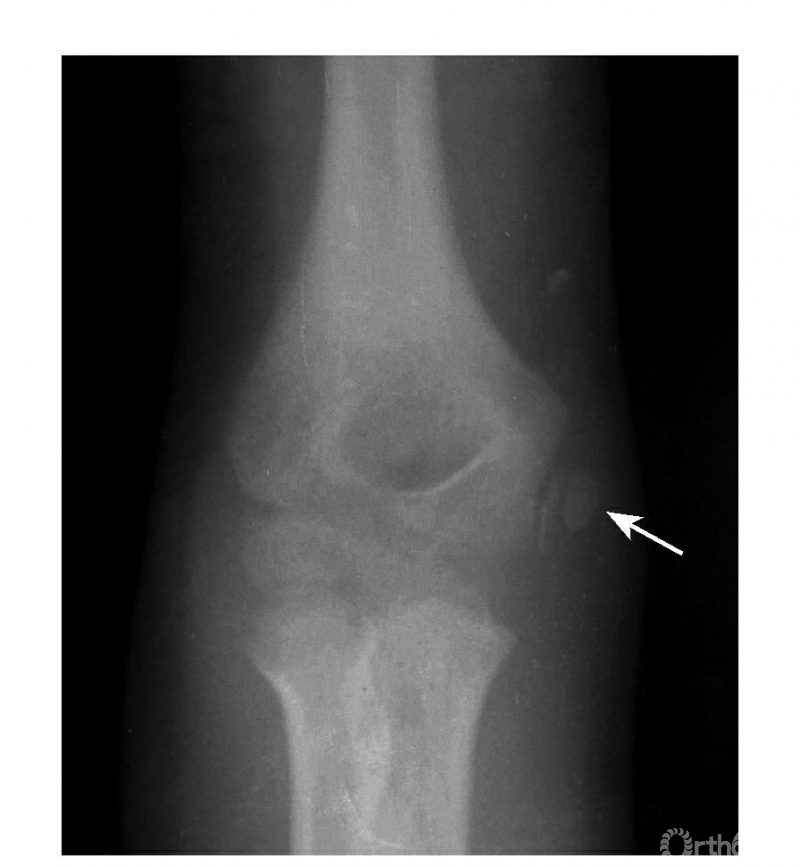

Ⅰ度损伤:

例:内上髁骨骺并带一皮质骨片略下移位(图3)

图3